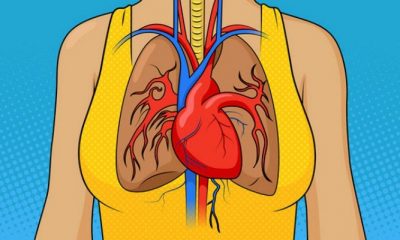

Καρδιακό επεισόδιο: Μην αγνοήσετε ΠΟΤΕ αυτά τα σημάδια [Inforgraphic]

31 Μαΐου 2018Αν σας προκύψει ξαφνικό πρόβλημα στην καρδιά, δεν είναι σίγουρο ότι θα νιώσετε τον πόνο στο...

Έναν Μήνα ΠΡΙΝ το Έμφραγμα, το Σώμα σου θα σου στείλει ΑΥΤΑ τα 8 Προειδοποιητικά Σημάδια. ΜΗΝ τα Αγνοήσεις!

9 Μαΐου 2018Οι καρδιακές προσβολές είναι τρομακτικές. Ειδικά, γιατί πολλές φορές είναι δύσκολο να προβλέψεις, πότε και ποιόν...